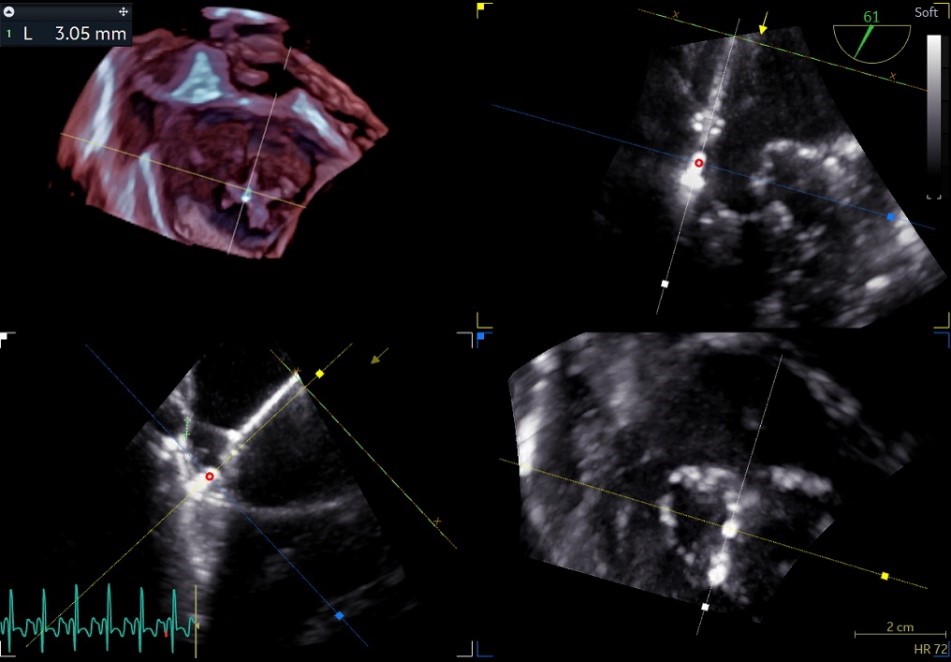

② 画迹法显示二尖瓣瓣口面积5.25cm²,平均跨瓣压差4.2mmHg;

③ 二尖瓣前叶(A1)长度28.5mm,二尖瓣后叶(P1)长度: 10.4mm;二尖瓣前叶(A2)长度28.4mm,二尖瓣后叶(P2)长度: 12.7mm二尖瓣前叶(A3)长度22.6mm,二尖瓣后叶(P3)长度: 11.5mm;

④ 3区前后叶对合gap 4.5mm,2区前后叶对合gap 3mm。

3区gap